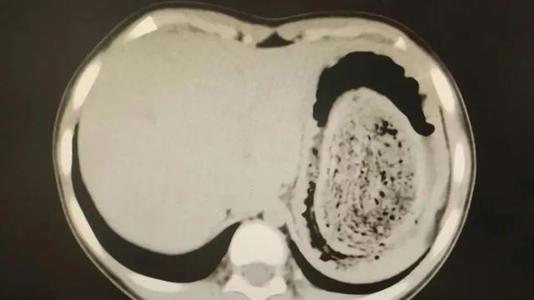

“心太大了!”福建,10岁女孩3年来经常肚子疼,家长带她看了多家医院都没有根治,直到又换了一家才发现,原来女孩一直在偷偷吃头发,导致胃里四分之三的空间是头发,而头发和食物结合变成了“胃石”,最终医生花了十几个小时,才将头发清理出来,网友:家人有真正关心孩子吗? 9月28日,在福建省儿童医院诊室里,福州10岁女孩小可的妈妈声音带着哭腔,攥着医生的白大褂不肯松手。 消化营养科副主任医师陈攸涛伸手一摸孩子的肚子,眉头立刻皱了起来。 女孩的腹腔深处有个坚硬的肿块,触感像块鹅卵石。 在胃镜探头伸进去的瞬间,显示屏上的画面让在场医护都倒吸一口凉气。 小可的胃里塞满了黑乎乎的毛发团,相互缠绕着占据了胃容量的四分之三。 边缘已经被胃酸侵蚀得坚硬如石,胃壁因为长期压迫变得红肿糜烂。 小可的妈妈这时才猛然想起被忽略的细节,三年前就见过她揪头发往嘴里塞,以为是小孩调皮,骂了两句就没管了。 原来,性格内向的小可不爱说话,在学校里也不太合群,每次考试没考好或者被老师批评后,就会偷偷拔自己的头发吃。 这些发丝在胃里无法消化,日复一日与食物残渣、胃酸混合,慢慢凝结成了致命的“胃石”。 不仅引发持续腹痛,还导致了缺铁性贫血。 为了保住孩子的胃,医生没有选择开腹手术,而是制定了保守治疗方案。 先让小可每天喝可乐软化胃石,可乐中的酸性物质能分解毛发间的黏连,这是临床验证过的有效方法。 三天后再用胃镜一点点将软化的头发团夹出来。 整个手术持续了十几个小时,当最后一团头发被取出时,护士用两个大号塑料盆才装下这些带着酸臭味的发丝,盆底还沉着不少食物残渣的碎屑。 术后第二天,小可终于能喝下一碗粥,脸上露出了久违的笑容。 据悉,孩子得的是‘长发公主综合征’,医学上叫毛发胃石症,本质是异食癖的严重并发症。 只要孩子持续一个月以上吃头发、泥土等非食物物质,就属于异食癖,80%都和心理问题有关。 的孩子压力不比大人小,功课负担、升学竞争、家庭争吵都可能让他们焦虑。 而吃头发时的咀嚼动作能刺激大脑释放镇静物质,成了他们缓解情绪的“秘密武器”。 少数孩子是因为缺锌、缺铁导致味觉错乱,但必须通过专业检测确诊,不能盲目补营养剂。 最让医生痛心的是家长的认知误区。 不少家长发现孩子吃头发后,第一反应是打骂训斥,结果反而让孩子的行为变得更隐蔽。 打骂只会让孩子更焦虑,还会让他们不敢说实话,延误最佳治疗时机。 其实早发现并不难。医生提醒家长,只要留意这些信号就能及时干预。 孩子头发有整齐的断口、书包里藏着毛发残渣、情绪不好时爱啃衣领,这些都是危险信号。 一旦发现,先带孩子做微量元素检测和B超,排除生理问题后,再找心理医生疏导情绪。 平时可以把孩子头发剪短,减少接触机会,睡前多陪孩子聊聊天,周末带他们出去玩耍,这些陪伴能极大缓解孩子的焦虑。 孩子的胃里不会凭空长出头发,就像他们的心里不会平白生出焦虑。 那些被大人当成“怪癖”的行为,或许正是孩子发出的求救信号。 比起手术台上十几个小时的艰难取石,更重要的是家长弯下腰的倾听和伸出手的陪伴。 毕竟守护孩子的心理健康,才是阻止“胃里长石头”的根本办法。 信息来源:潇湘晨报2025-09-29发布:福建一10岁女孩长期腹痛,医生一查傻眼:从肚子里取出两大盆头发!